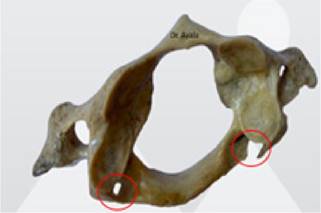

En la figura N° 2. se aprecia la presencia del foramen y una osificación incompleta encerradas en círculos rojos.

Fuente: elaboración propia, 2024

Figura 2: Vertebra C1 con detalles normales